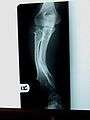

Multiple osteochondromas causing deformity of the forearm (shortening of the Radius with secondary bowing of the Ulna).